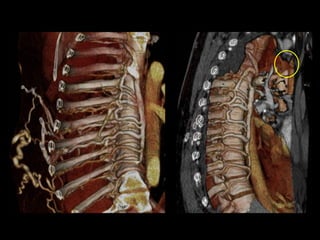

65M with metastatic lung ca and recent PEs. An IVC filter was placed but did

not fully deploy. A second IVC filter was placed above the first one.

120cc contrast, diagnostic delay = 70sec